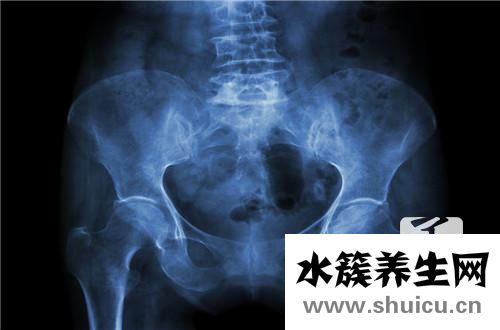

盆底肌并不是一塊肌肉,而是封閉骨盆底的肌肉群。

由一對(duì)肛提肌和一對(duì)尾骨肌構(gòu)成,這一肌肉群猶如一張“吊網(wǎng)”尿道、膀胱、陰道、子宮、直腸等臟器被這張“網(wǎng)”緊緊吊住。

當(dāng)盆腔肌肉功能正常時(shí),這張網(wǎng)通過(guò)這些結(jié)構(gòu)的收縮和緊張來(lái)抵抗腹壓增加,從而支撐盆腔臟器。